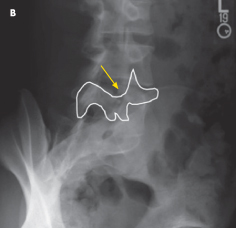

spondylolysis

Martha A. Hellems, MD; E. Michael Villareal, MD

<p class="p1"><img src="/sites/default/files/transfer/1207CFP_PCSpondylo_B.jpg" width="90" height="90" style="float: left; margin:...